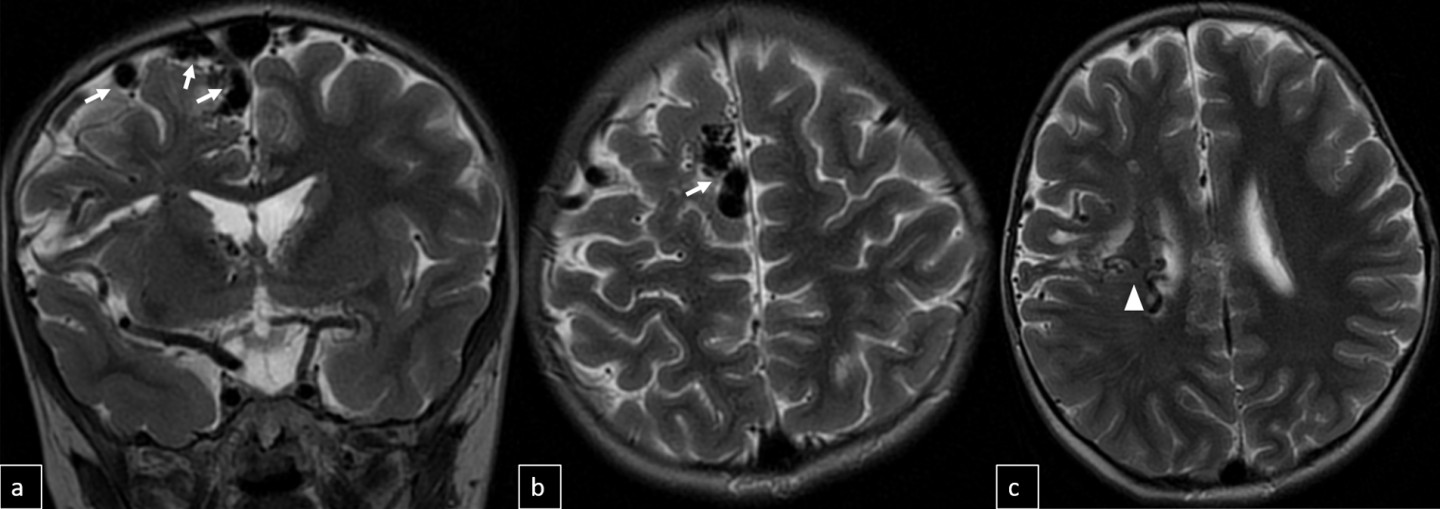

Cranial MRI demonstrated a dilated tortuous arteriovenous malformation in the right frontal lobe, fed by the distal branches of the anterior cerebral artery (ACA), draining into the cortical veins and central nervous system. A second AVM was detected in the corona radiata, with dilated parietotemporal draining veins fed by perisylvian branches of the middle cerebral artery (MCA), draining into the internal cerebral veins and the straight sinus via pericallosal dilated venous structures (Figure 2, Figure 3, Figure 4). At the level of the basal ganglia and mesencephalon, arterial angiomatosis resembling the classic “moyamoya” appearance was observed (Figure 5).